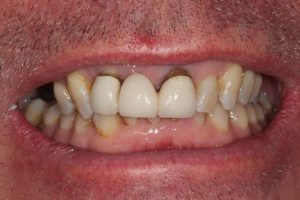

Upper Front Tooth Implant

This patient had broken their upper front tooth and the exisitng dental crown had fallen off. The underlying root was unfortunatley irreparable.

The dental root was subsequently removed and an implant placed at the same time. The implant had a temporary crown placedon the same day.

The ‘After’ photos shows the final crown that was made after 3 months. The implant crown was made to match the form and colour of the exisiting teeth to give an overall natural aesthetic finish.